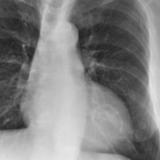

Mitral Valve Disease

Album: Mitral Valve Disease

Date: 03/17/2004

Size: 30 items

Views: 42308